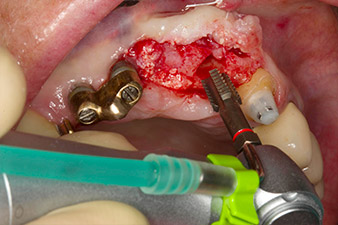

Une fois la cicatrisation primaire obtenue, les tissus mous ont été formés à l'aide du bridge doublé à la base. Deux mois plus tard, la zone a été exposée au moyen d'une incision de la crête alvéolaire légèrement orientée côté palatin (Fig 2). Les dimensions de l'os alvéolaire se sont avérées suffisantes en position 22. Les Figures 2 et 4 illustrent la préparation du lit implantaire, le taraudage et la pose de l'implant à l'aide de l'Implantmed.